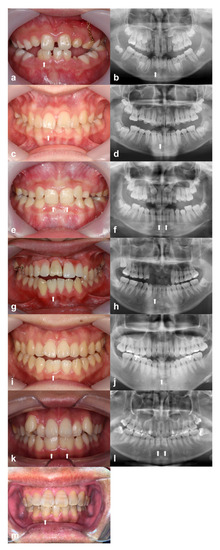

Figure 1 shows the six family trees. Figure 2 shows intraoral photographs and panoramic radiographs of the patients with fused teeth. Table 1 summarises patient sex, the positions of the fused teeth, and the inclusion type (monoliteral or bilateral).

Figure 2.

Intraoral and panoramic radiographs, respectively, of: (a,b) patient A-1 (Family A); (c,d) patient B-1 (Family B); (e,f) patient C-1 (Family C); (g,h) patient D-1 (Family D); (i,j) patient E-1 (Family E); (k,l) patient F-1 (Family F); (m) intraoral photograph of patient F-2 (Family F). White arrows indicate fused teeth.